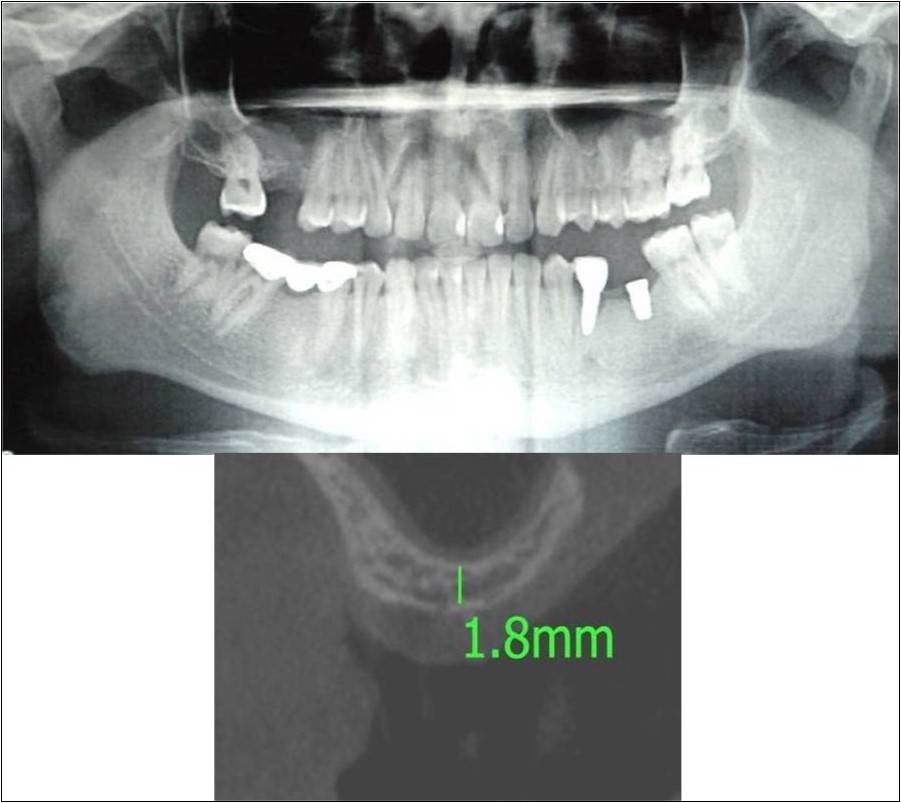

Case Report 3:

A 75 years old male patient reported to the Department of Oral and Maxillofacial Surgery, D.A.P.M.R.V Dental College and Hospital seeking options for replacement of his missing tooth in right upper back tooth region with a fixed prosthesis. The tooth was extracted around 10 years ago because of pain and infection associated with the tooth. No prosthetic rehabilitation was carried-out in the past. 16 was found to be missing and the patient reported that healing was uneventful post-extraction of the tooth. The patient was a controlled diabetic and hypertensive and was on medications for the same. Patient did not give history of any existing sinus pathologies. All possible rehabilitative options were explained to the patient and a treatment plan of replacement of missing 16 with implant supported prosthesis using one dental implant was finalized

Clinical and Radiological Assessment:

1.Partially edentulous maxillary arch with missing 16;

2.Increased pneumatisation of right maxillary sinus;

3.Height of available bone- 5.3mm;

4.Transverse thickness of available bone (CBCT evaluation)- 10.2mm;

5.Inter-ridge space adequate to place implant (10mm).

Treatment:

Patient underwent the procedure of indirect sinus elevation using sinus osteotomes in relation to 16 region. Calcium phosphosilicate putty was dispensed as the graft material through the crestal osteotomy site to maintain the elevated sinus membrane followed by placement of a dental implant measuring 5 x 10mm under local anaesthesia and strict aseptic protocols. The implant was allowed to osseo-integrate for a period of six months during which the patient was followed-up periodically and was assessed for peri-implantitis, crestal bone loss and mobility. At the end of 6 months, a repeat CBCT scan was advised to evaluate the increase in bone height. (Figure 11a,b, pre-treatment; Figure 12a,b, post-treatment)

Figure 11.(a,b) Pre-treatment OPG and cross section of CBCT showing residual alveolar bone height for Case No.3

Figure 12.(a,b) Post-treatment OPG and cross section of CBCT showing residual alveolar bone height for Case No.3;